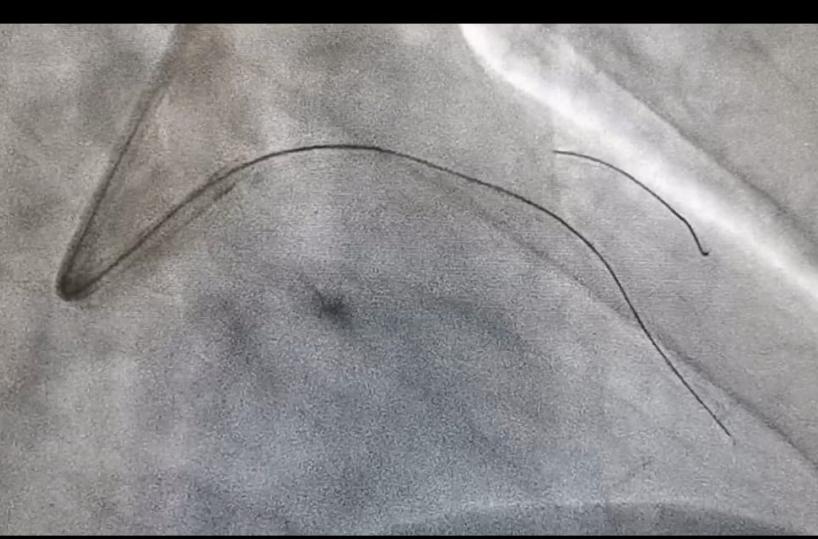

La cardiologia dell’ospedale San Paolo di Bari è tra i primi centri in Italia ad aver impiegato una tecnica innovativa per trattare le occlusioni coronariche croniche totali. La procedura, spiega la Asl Bari in una nota, si avvale di un micro catetere, mai usato finora, grazie al quale è possibile ripristinare il corretto afflusso di sangue al cuore, con un intervento mininvasivo che evita di ricorrere all’unico approccio chirurgico del bypass aorto coronarico o, in alcuni casi, di non poter procedere con la rivascolarizzazione.

La procedura ha curato un uomo di 69 anni affetto da occlusione dell’arteria interventricolare anteriore, la più importante delle coronarie. Ad eseguire l’intervento è stato il dottor David Rutigliano con il supporto dell’equipe medica e infermieristica del laboratorio di Emodinamica del San Paolo.